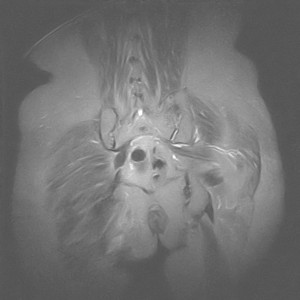

图像太差了 1、右侧臀肌旁脓肿? 建议增强 2、左侧股骨头坏死并半脱位

1、左侧股骨头坏死并髋关节半脱位;

2、右侧臀肌感染,(可能褥疮所致)